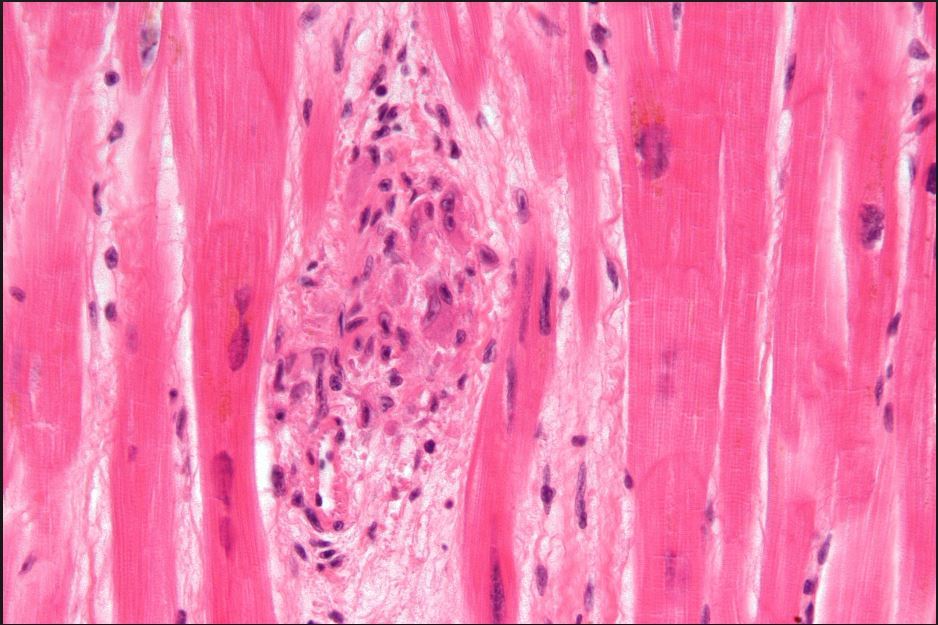

Q

What cardiac tumor is being shown?

A

Rhabdomyoma

MOST COMMONLY IN LEFT VENTRICLE

Most common primary cardiac tumor of

infancy and childhood

May be sporadic, but >50% associated with TS

Eosinophilic, polygonal cells with large glycogen-rich cytoplasmic vacuoles with stranding “spider cells”